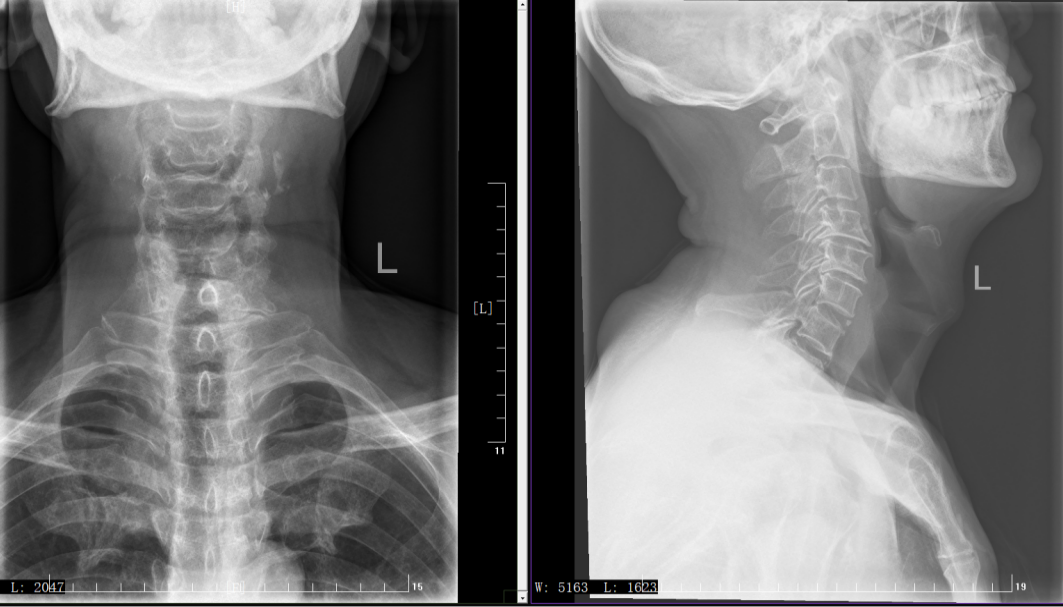

入院后的影像学检查很快揪出了病因——南大爷的颈4-5、颈5-6两节颈椎间盘同时突出,像两块错位的软垫,死死顶住了后方的脊髓和神经根。更棘手的是,椎体已经出现不稳,保守治疗根本无力回天。